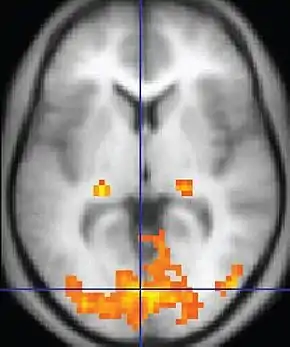

| Functional MRI (fMRI) | Blood-oxygen-level dependent imaging | BOLD | Changes in oxygen saturation-dependent magnetism of hemoglobin reflects tissue activity.[29] | Localizing brain activity from performing an assigned task (e.g. talking, moving fingers) before surgery, also used in research of cognition.[30] |  |

Functional MRI

Functional MRI (fMRI) measures signal changes in the brain that are due to changing neural activity. It is used to understand how different parts of the brain respond to external stimuli or passive activity in a resting state, and has applications in behavioral and cognitive research, and in planning neurosurgery of eloquent brain areas.[48][49] Researchers use statistical methods to construct a 3-D parametric map of the brain indicating the regions of the cortex that demonstrate a significant change in activity in response to the task. Compared to anatomical T1W imaging, the brain is scanned at lower spatial resolution but at a higher temporal resolution (typically once every 2–3 seconds). Increases in neural activity cause changes in the MR signal via T*

2 changes;[50] this mechanism is referred to as the BOLD (blood-oxygen-level dependent) effect. Increased neural activity causes an increased demand for oxygen, and the vascular system actually overcompensates for this, increasing the amount of oxygenated hemoglobin relative to deoxygenated hemoglobin. Because deoxygenated hemoglobin attenuates the MR signal, the vascular response leads to a signal increase that is related to the neural activity. The precise nature of the relationship between neural activity and the BOLD signal is a subject of current research. The BOLD effect also allows for the generation of high resolution 3D maps of the venous vasculature within neural tissue.

While BOLD signal analysis is the most common method employed for neuroscience studies in human subjects, the flexible nature of MR imaging provides means to sensitize the signal to other aspects of the blood supply. Alternative techniques employ arterial spin labeling (ASL) or weighting the MRI signal by cerebral blood flow (CBF) and cerebral blood volume (CBV). The CBV method requires injection of a class of MRI contrast agents that are now in human clinical trials. Because this method has been shown to be far more sensitive than the BOLD technique in preclinical studies, it may potentially expand the role of fMRI in clinical applications. The CBF method provides more quantitative information than the BOLD signal, albeit at a significant loss of detection sensitivity.